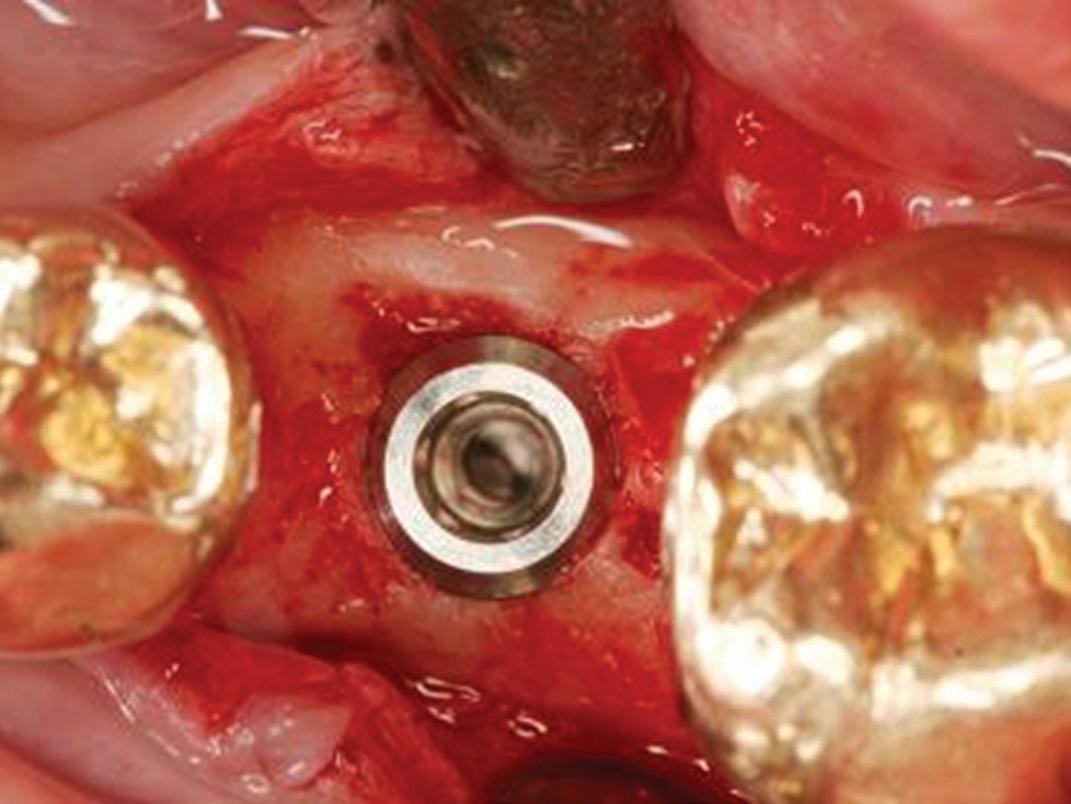

If no perforation is present, the implant is placed in the ideal positioning determined from the preoperative planning (Fig 7). The implant handpiece is preferred for placing the implant fixture because it provides a torque reading in real time as the implant is being placed. The implant motor is electively set to 35 N/cm, and the handpiece will stop advancing the implant once it reaches that reading. The hand driver is then used to finish fully seating the implant at

Fig 7. The implant positioning confirms excellent buccal bone width that will promote long-term stability.